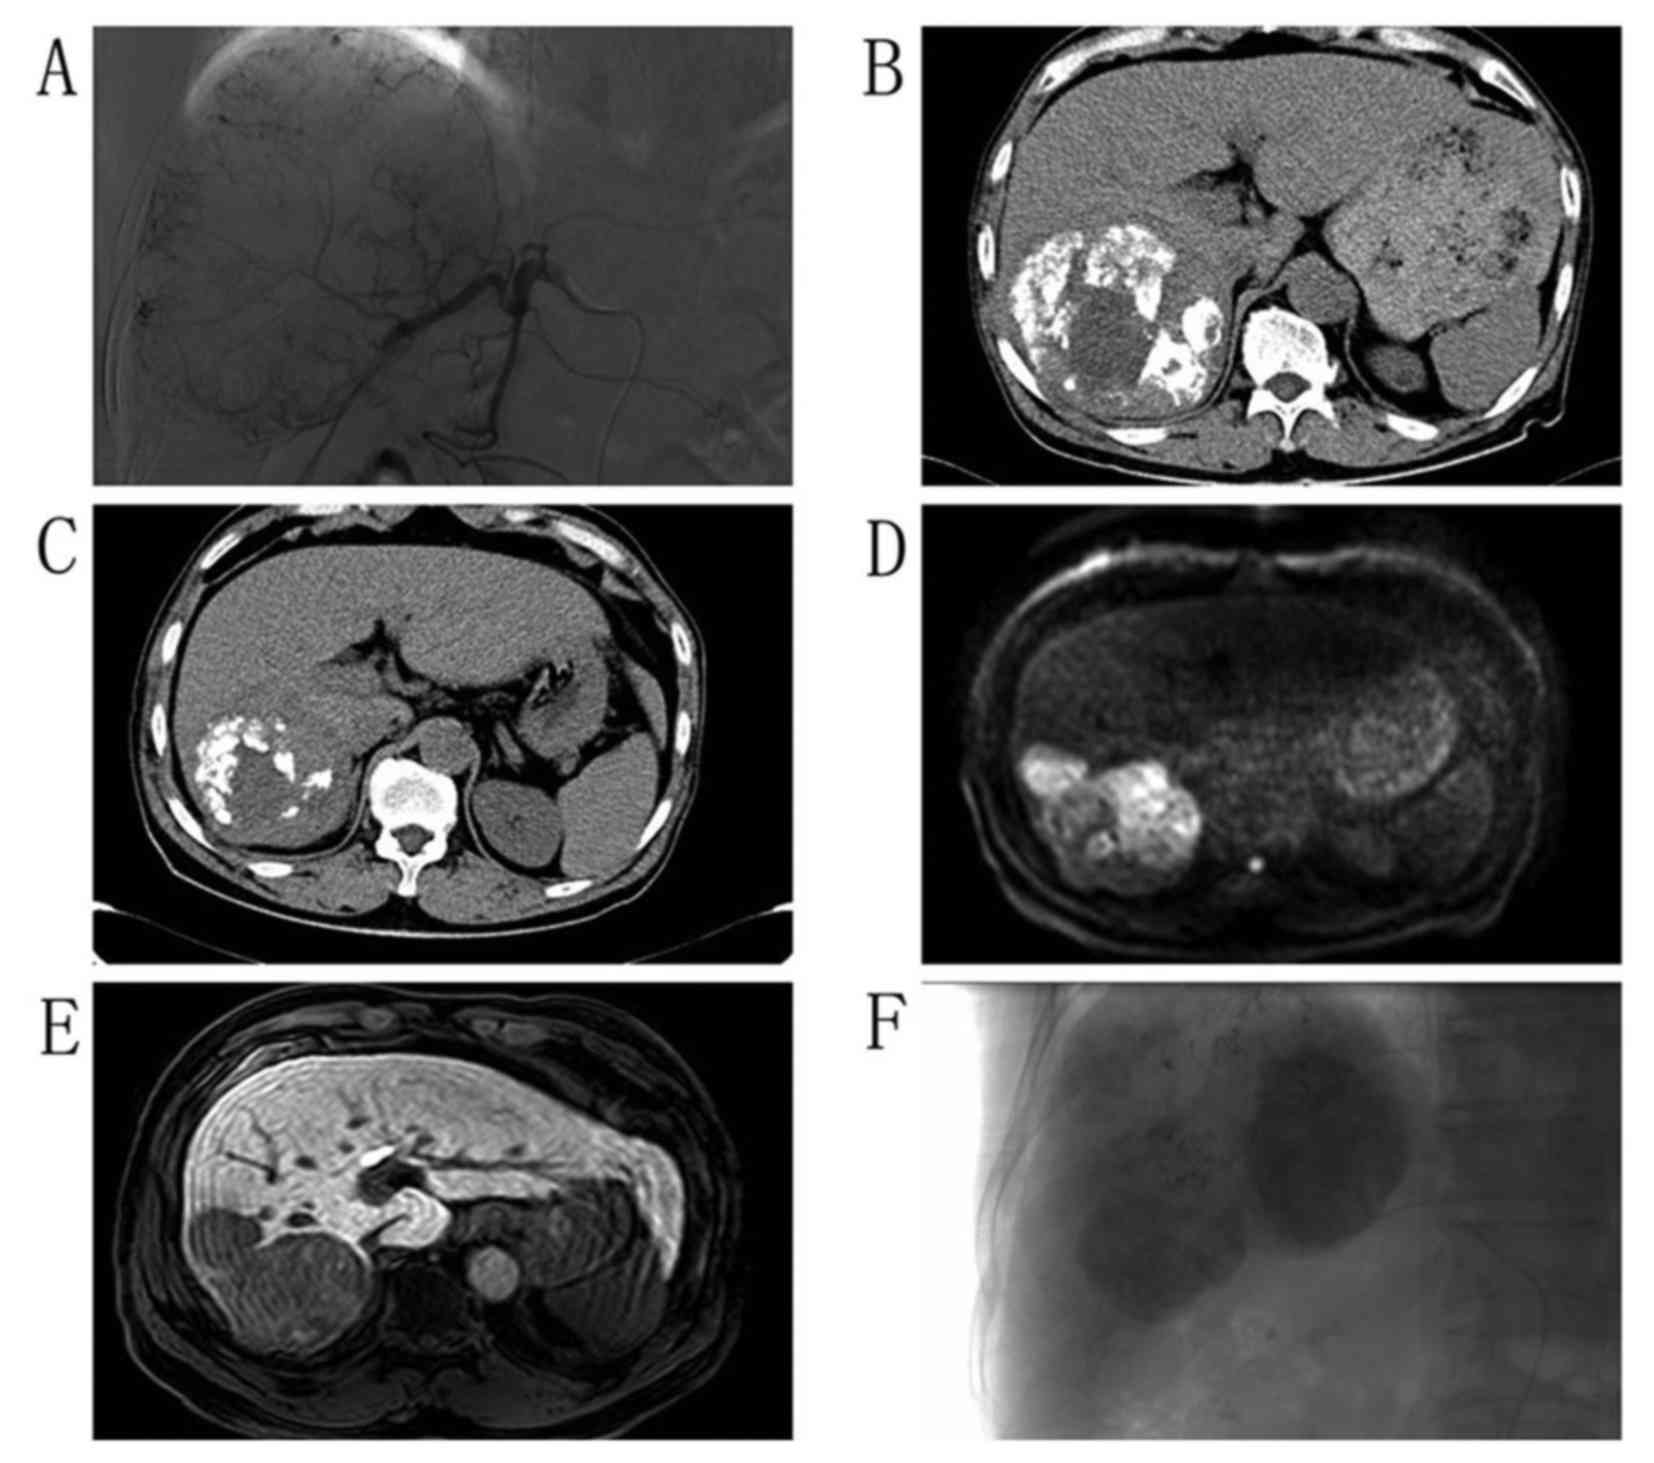

Imaging and digital subtraction angiography findings for patients who received a second TACE treatment were reviewed, and the Response Evaluation Criteria for Solid Tumors (24) were modified and applied for assessment of the progression of HCC. During imaging analysis, tumor progression was reported if the largest diameter of the mass had increased since the previous examination or if a new mass or nodule was noted beside the previous mass (Fig. 5). On the digital subtraction angiograph, tumor progression was considered if the feeding blood vessels had increased in size or vascularity and were disordered. However, if the mass did not exhibit any marked change in size or vascularity, the tumor was not considered to have progressed and remained under control (Fig. 6).

Representative images of a 59-year-old male treatment-naïve patient with hepatocellular carcinoma. (A) Angiography of the tumor revealed rich vascularity, therefore TACE was performed. (B) At 1 month post-TACE, computed tomography examination revealed moderate focal iodine oil deposits, thus the patient received a second TACE treatment. (C) After 4 months, the tumor size exhibited no marked change. (D) The patient received a third TACE treatment and diffusion weighted imaging revealed a new developed nodule with abnormal restricted diffusion, suggesting progression, 1 year later. (E) Gd-EOB-DTPA-enhanced MRI 30 min after intravenous injection of Gd-EOB-DTPA revealed a new hypo-intensity nodule beside the previous mass. (F) Digital subtraction angiography confirmed rich blood vessels. This case was considered as tumor progression. TACE, transcatheter arterial chemoembolization; MRI, magnetic resonance imaging; Gd-EOB-DTPA, gadolinium ethoxybenzyl diethylenetriamine pentaacetic acid.